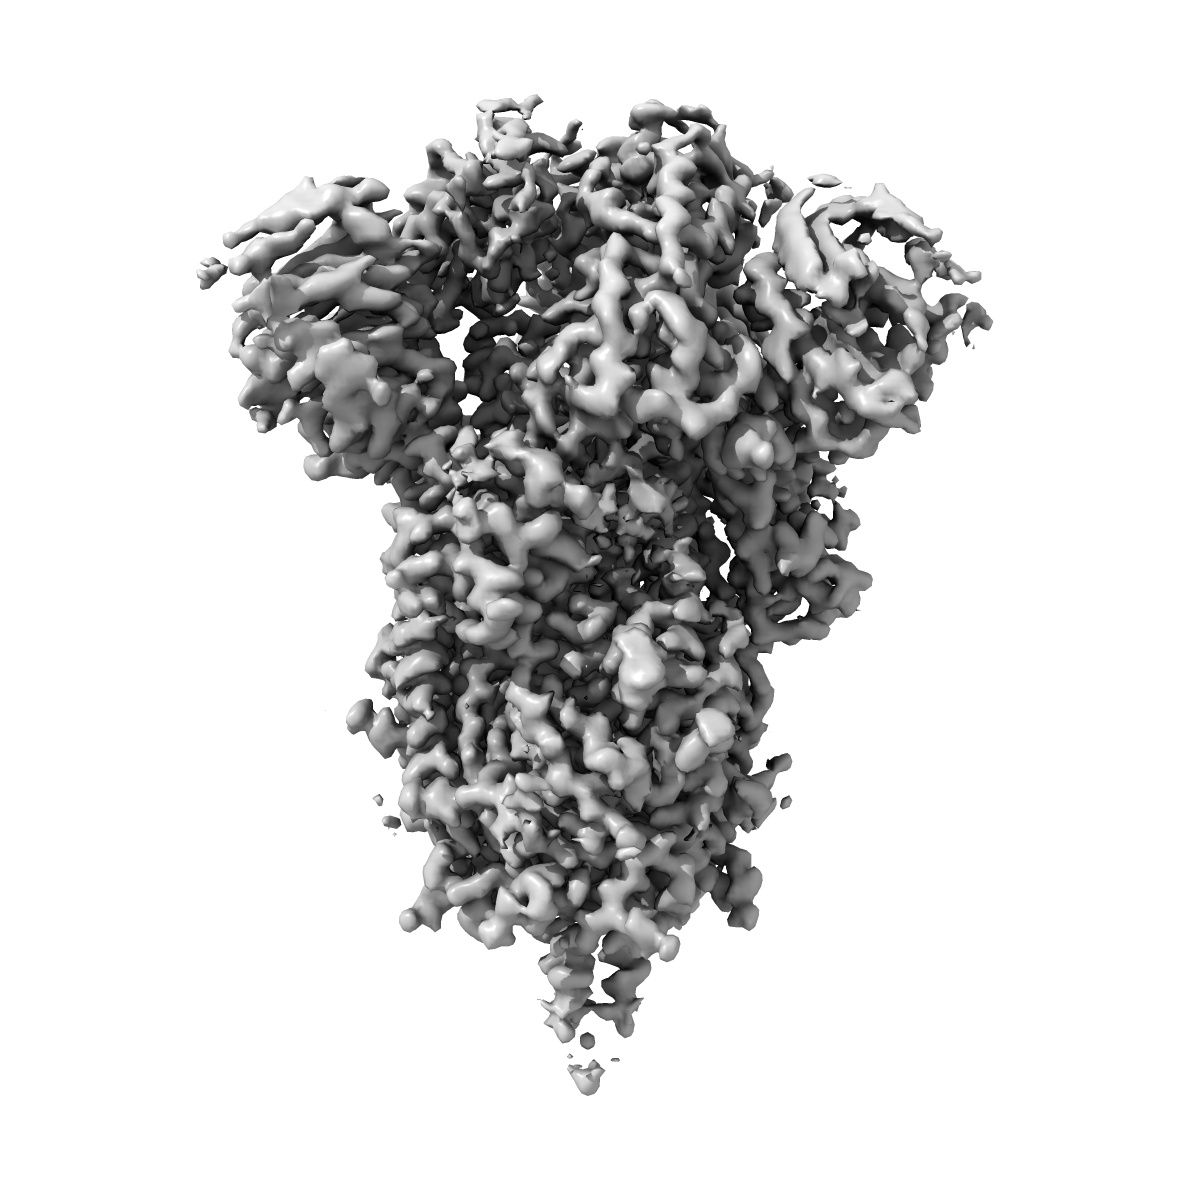

Cryo-EM structure of SARS-CoV-2 Spike Proteins on intact virions: B.1 variant 3 closed RBDs

Virion morphology and on-virus spike protein structures of diverse SARS-CoV-2 variants.

Ke Z , Peacock TP , Brown JC , Sheppard CM , Croll TI , Kotecha A , Goldhill DH , Barclay WS , Briggs JAG

(2024) EMBO J , 43 , 6469 - 6495